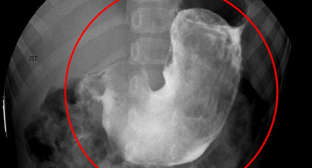

Après plusieurs examens, les docteurs ont fini par découvrir que la petite avait une importante masse dans l’abdomen. Il s’agissait d’une grosse boule de cheveux accumulés dans l’estomac. Des radiographies montrent l’importante masse coincée dans son ventre, mais également une lésion, rapporte TVA nouvelles.

L’enfant a finalement été diagnostiquée avec le syndrome de Rapunzel, une très rare condition médicale dans laquelle la boule de cheveux, appelée trichobezar, est coincée dans l’estomac et s’étire jusqu’au colon. Ce syndrome est extrêmement rare. Seulement 120 cas ont été rapportés dans la littérature médicale. La plupart du temps ce sont des femmes qui en sont atteintes.

Lors de l’opération, les médecins ont retiré près de 125 grammes de cheveux de l’estomac de la jeune fille. L’opération a duré près de deux heures.